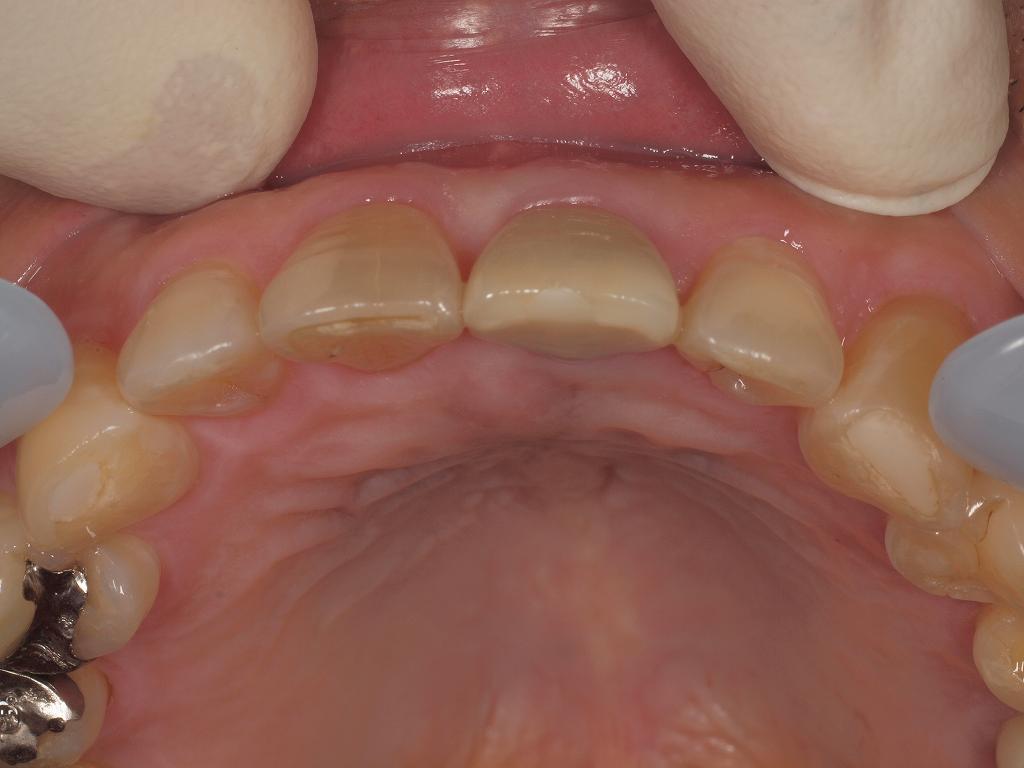

咬合面から

咬合面から見ても綺麗に仕上がっています